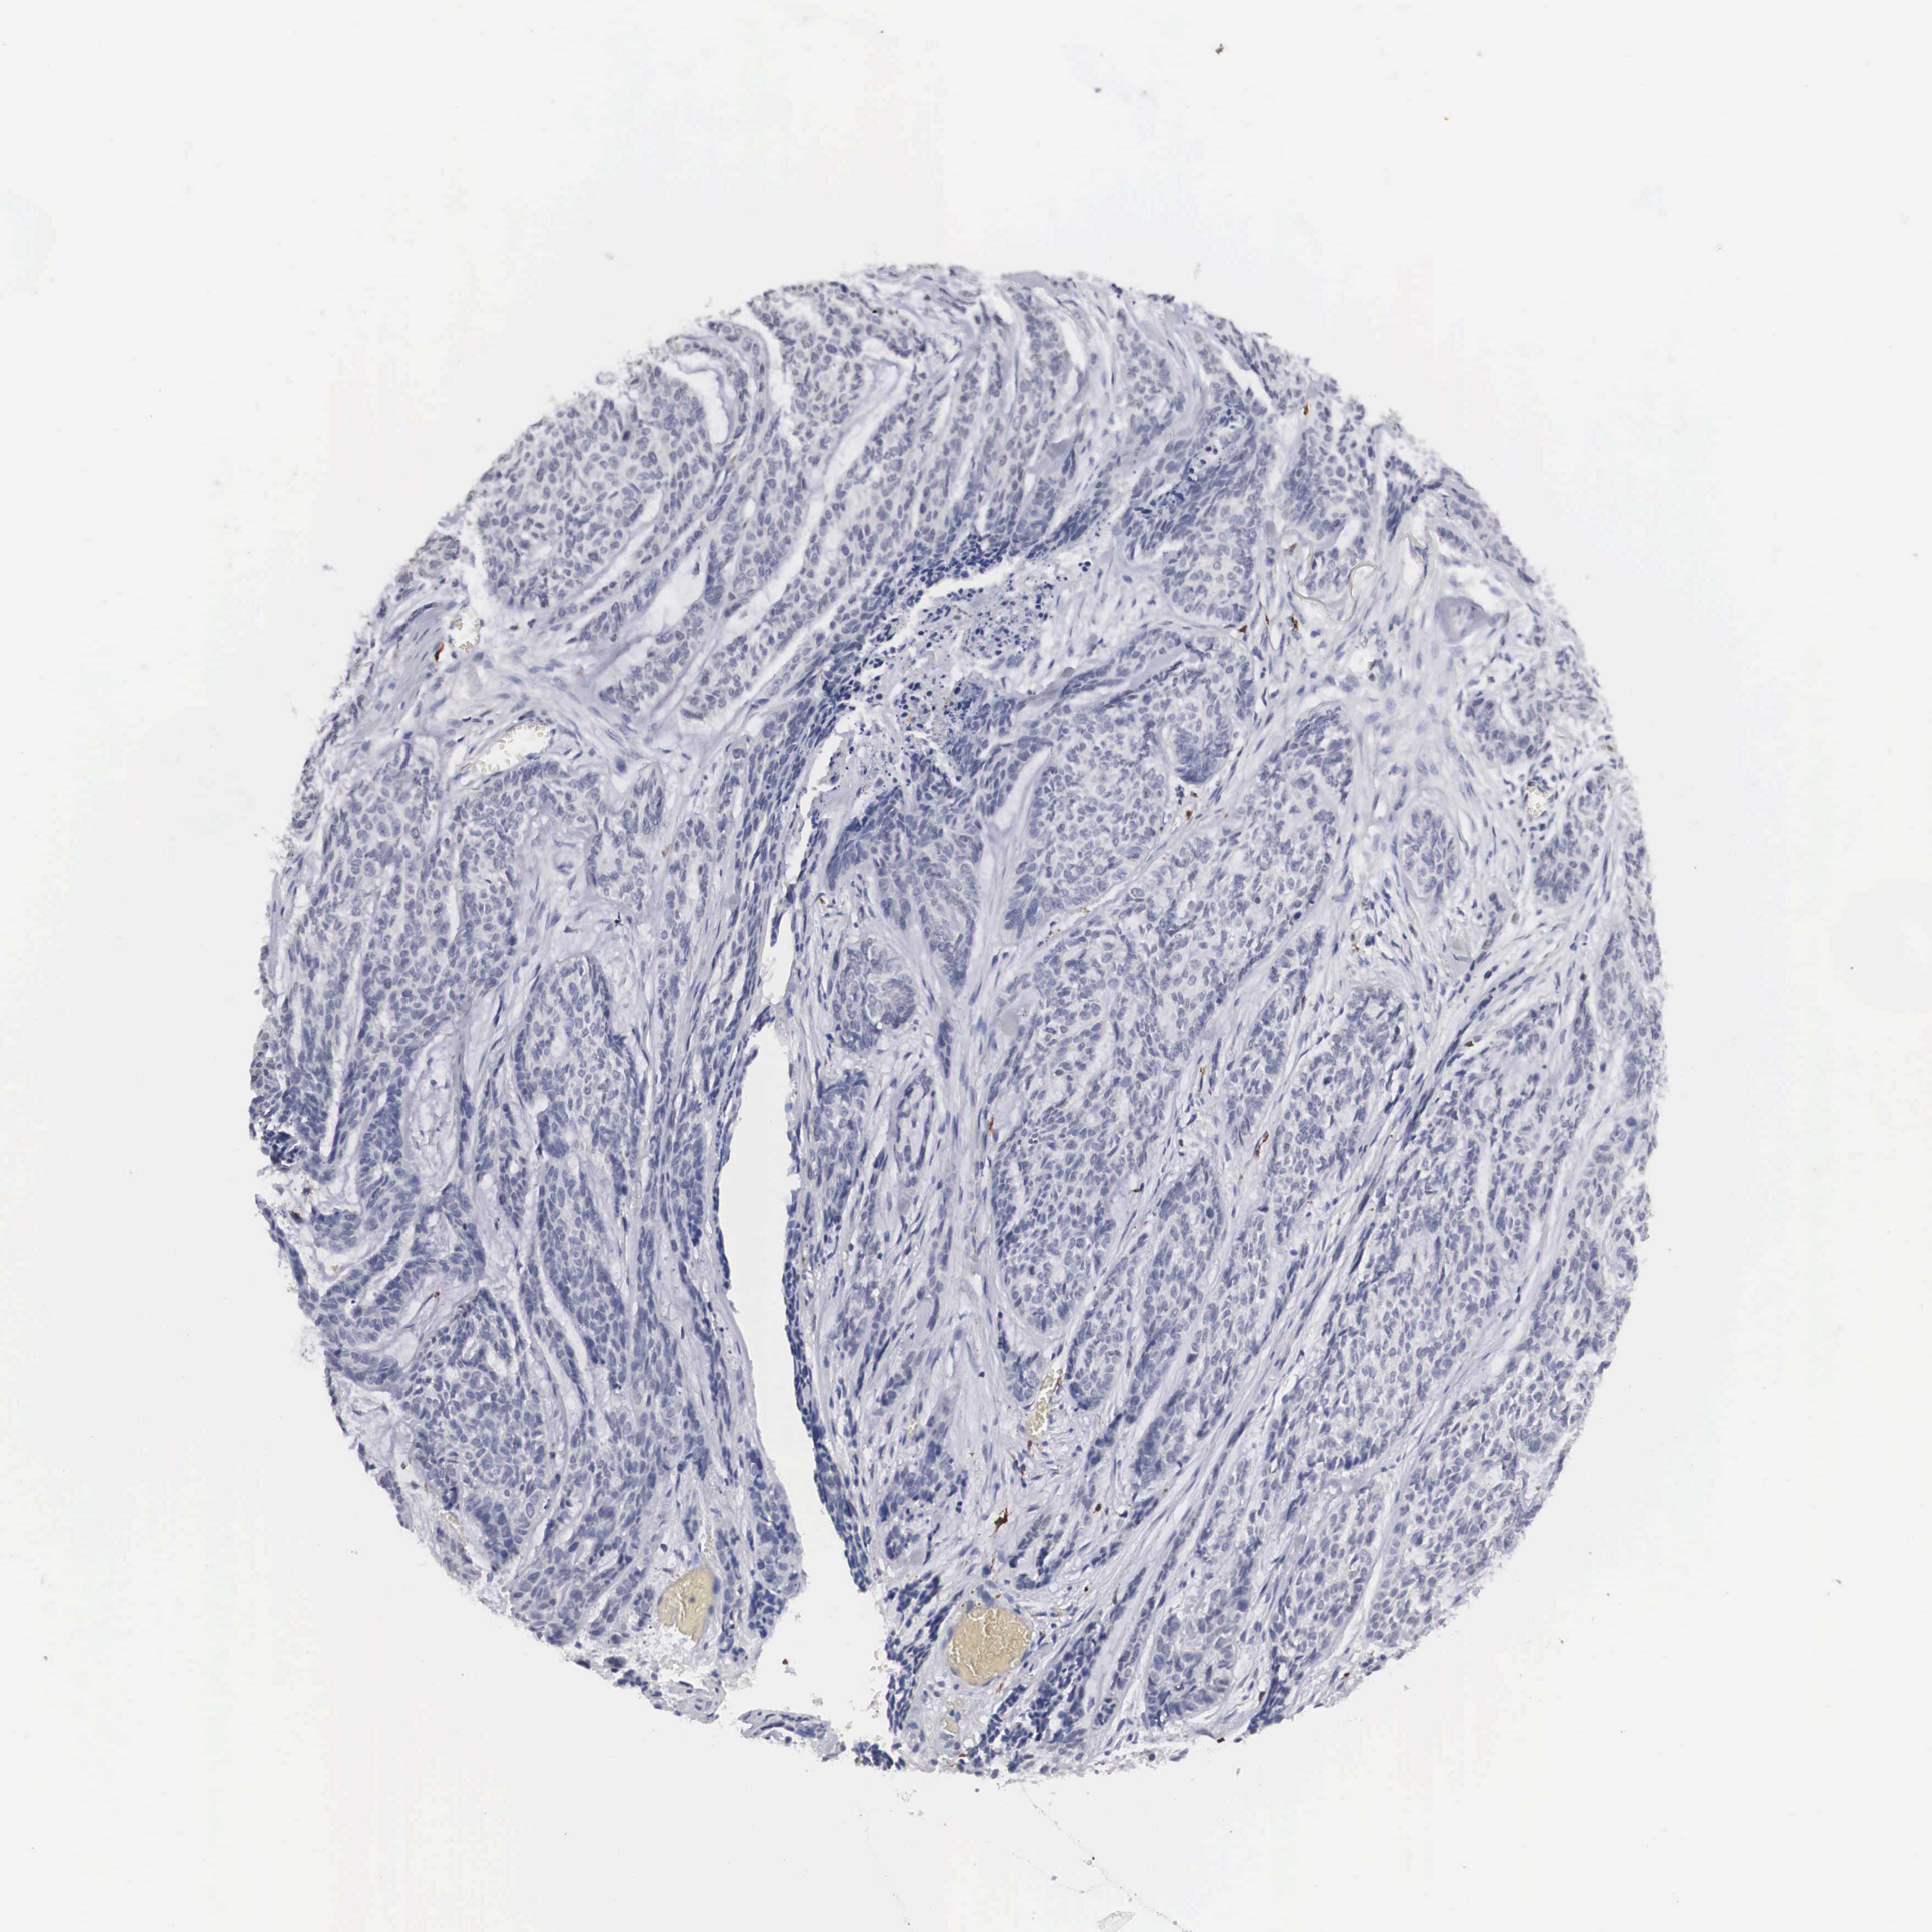

Basal cell and squamous cell cancer

SKIN CANCER - Protein expressioni

A mouse-over function shows sample information and annotation data. Click on an image to view it in a full screen mode. Samples can be filtered based on level of antibody staining by selecting one or several of the following categories: high, medium, low and not detected. The assay and annotation is described here.

Antibody stainingi

Antibody staining in the annotated cell types in the current human tissue is reported as not detected, low, medium, or high, based on conventional immunohistochemistry profiling in selected tissues. This score is based on the combination of the staining intensity and fraction of stained cells.

Each image is clickable and will lead to virtual microscopy that enables deeper exploration of all samples and also displays staining intensity scores, fraction scores and subcellular localization as well as patient and tissue information for each sample.

Antibody HPA000635

Antibody CAB017444

Squamous cell carcinoma, metastatic, NOS